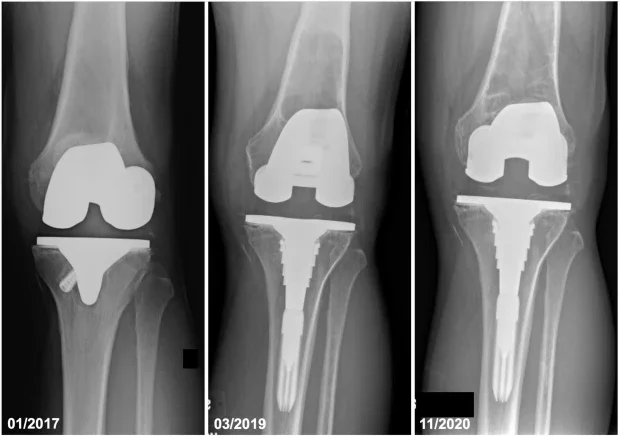

Перипротезна остеолиза

Този вид остеолиза възниква в резултат на механичното износване на изкуствена става - еднопротеза. Въпреки, че се случва рядко, някои материали като полиетилен могат да се разпаднат с времето и да причинят натрупване на частици в околните тъкани. В резултат на това костта започва да се разгражда поради възпалението, което води до перипротезна остеолиза.

Ендопротезиране - Общоприетото обяснение за остеолизата при смяна на става се свързва с частици отделени от нейното износване. Тъй като тялото се опитва да отстрани тези частици (обикновено състоящи се от пластмаса или метал), това предизвиква автоимунна реакция, която причинява резорбция на костната тъкан. Съобщава се, че остеолизата се появява 12 месеца след имплантирането и обикновено е прогресивна. Това може да изисква ревизионна операция (подмяна на протезата). Въпреки че самата остеолиза е клинично асимптоматична, тя може да доведе до разхлабване на импланта или счупване на костта, което от своя страна причинява сериозни медицински проблеми.

Остеолиза при ендопротезиране - При нея симптомите се появяват много късно, след като е настъпила значителна костна загуба. Поради тази причина пациентите, претърпели операция за смяна на става, трябва периодично да правят контролни рентгенови снимки. Когато се появят, симптомите на остеолиза около ставната протеза обикновено са свързани с разхлабването на импланта. Те включват:

- Нестабилност в близост в областта на ортопедични импланти: следствие от загубата на костна тъкан, имплатите могат да се разхлабят и да станат нестабилни. Това налага операция за ревизия и евентуална смяна.

Изображение: arthroplastytoday.org/ Periprosthetic Femur Fracture Through a Large Osteolytic Lesion After Total Knee Arthroplasty/ CC BY-NC-ND 4.0

- Ревизия на импланти при перипротезна остеолиза

Остеолиза при ендопротезиране - Ако се открие рано, могат да се използват различни подходи за контрол на възпалението и предотвратяване на по-нататъшна остеолиза. Ако костната загуба е обширна, лечението може да изисква операция за ревизия на изкуствената става (например ревизия на тазобедрената става или ревизия на колянната става)